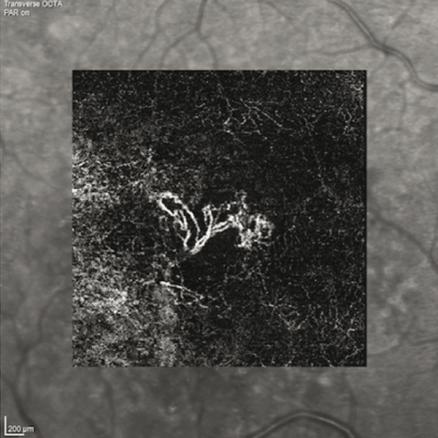

© Jennifer Marie-Louise, Ramin Tadayoni (La Revue du Praticien) Néovaisseau sous-rétinien de la dégénérescence maculaire liée à l'âge.